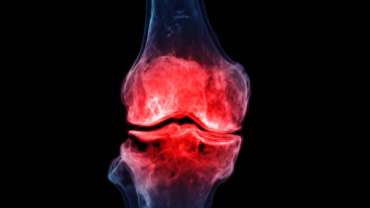

Dizin ön kısmında bulunan ve dizin stabilitesini sağlayan bir bağın yaralanmasıdır. Ön çapraz bağ kopması genellikle ani bir hareket veya travma sonucunda meydana gelir. Dizin…

Diz eklemindeki hasar veya aşınmış dokuların yerine suni protezlerin yerleştirildiği işlemdir. Ameliyat, dizdeki ağrıyı azaltmak, hareket kabiliyetini geri kazanmak ve yaşam kalitesini artırmak için yapılır.…